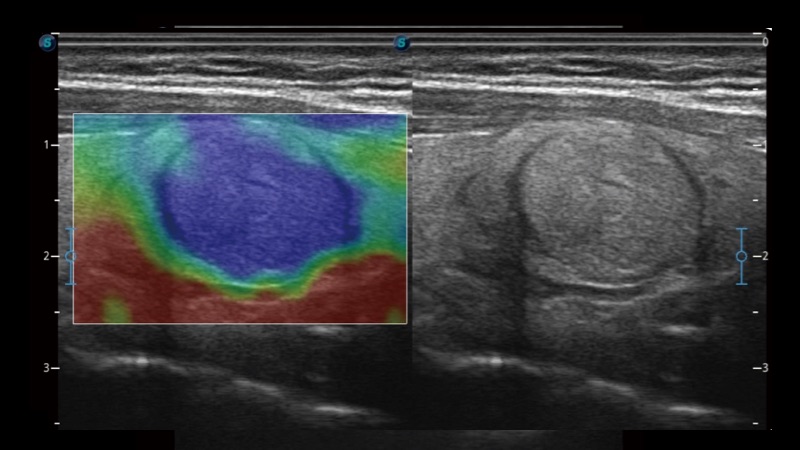

弹性成像

弹性成像无需高频度外力作用可真实反映组织的形变,具有良好的重复性,更早地洞察潜在的病理学特征。

临床图像